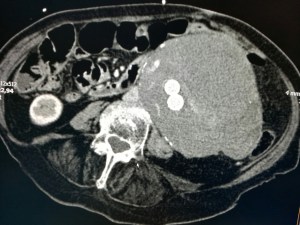

AAA3